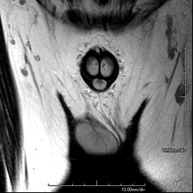

Prova diagnòstica no invasiva que consisteix en l'obtenció d'imatges d'alta definició anatòmica de la pelvis mitjançant l'ús d'un camp electromagnètic i ones de ràdio (amb un emissor i un receptor). No utilitza radiació ionitzant. Es realitza per a l'estudi de patologies d'úter, d'ovari, de trompes i de vagina, ja siguin d'origen tumoral, inflamatori o vascular. També permet valorar les estructures adjacents localitzades a la pelvis i la identificació de les seves alteracions. De vegades és necessari l'ús de contrast intravenós (Gadolini) per caracteritzar les lesions. - RM Pelvis masculina

Prova diagnòstica no invasiva que consisteix en l'obtenció d'imatges d'alta definició anatòmica de la pelvis masculina mitjançant l'ús d'un camp electromagnètic i ones de ràdio (amb un emissor i un receptor). No utilitza radiació ionitzant. No requereix preparació prèvia. En algunes ocasions necessita l'ús de contrast paramagnètic (Gadolini) per caracteritzar les lesions. Aquesta prova permet valorar òrgans com la bufeta urinària, la unió entre els urèters i la bufeta, la pròstata, les vesícules seminals, la uretra i els ossos de la pelvis, entre d'altres. - RM de Fetge